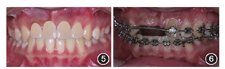

覆盖异常。75不松动,牙根部分吸收,患者拟行非减数矫治故暂时保留。上前牙区多个美学缺陷拟通过多学科联合治疗方案解决。正畸治疗解决牙齿排列及咬合问题,患者治疗前上中线右偏1.5 mm,上前牙原有间隙12 mm,种植修复11、12需14 mm间隙,需正畸扩展2 mm并解决中线右偏。对

牙缺失致41—43垂直向伸长1.5 mm,需正畸压低,建立正常覆

覆盖,为种植提供垂直向空间;对11位点水平向骨缺损进行骨增量,对11、12位点进行即刻种植即刻修复治疗,利用临时修复体进行软组织成形,最终行12、11、21冠修复(图5)。

像

像使用直丝弓排齐整平、扩展间隙和精细调整。推簧推21向远中(图6),扩展缺牙区2 mm间隙同时解决中线右偏,关闭22—24间散在间隙;压低下颌右侧前牙,纠正前牙区覆

覆盖。矫治完成后配戴透明压膜保持器(图7)。